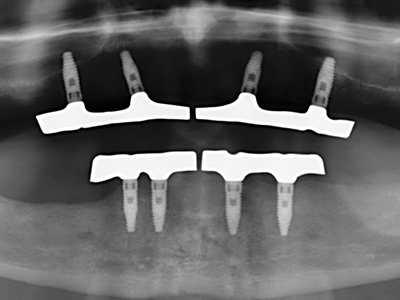

Фиг. 11: Следоперативната панорамна снимка показва вертикалната аугментация и синус лифта.

Фиг. 12: След шест месеца на заздравяване, алвеоларният гребен е добре оразмерен триизмерно.

Фиг. 15: Прегледът на рентгеновата снимка след 1 година показва стабилно състояние на нивото на костта.